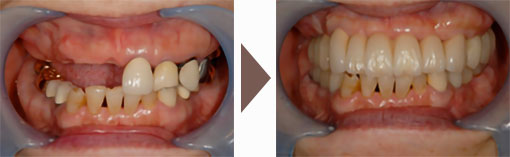

この方々は、毎日しっかり歯磨きをされていましたが、この写真ように多くの歯を失うことになりました。しっかりとケアしていたにも関わらず、なぜ歯を失うことになってしまったのでしょう?

その原因は、かみ合わせの悪さでした。

かみ合わせの悪さは、歯並びだけの問題ではなく、虫歯治療で入れたつめ物のバランスの悪さ、入れ歯の未使用といったものから、加齢による歯のすり減りなど、いくつかの原因によって引き起こされます。

かみ合わせが悪いと、一部の歯に大きな負担がかかります。噛むときに歯にかかる力は、成人男性の平均で約60kgと言われていますが、長年、その力を過剰に受け続けた歯は、その負担に耐えきれず、ある年齢に達したときにダメになってしまいます。

1本の歯がダメになると、周りの歯にもズレやゆがみなどの問題が広がり、かみ合わせの悪さがどんどん進行して、最終的にの画像のような状態まで悪化してしまいます。